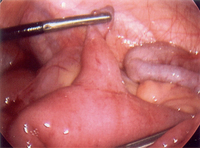

Torção de apêndice testicular resultante em infarto agudo

Do acervo de Dr. KuoJen Tsao; usado com permissão